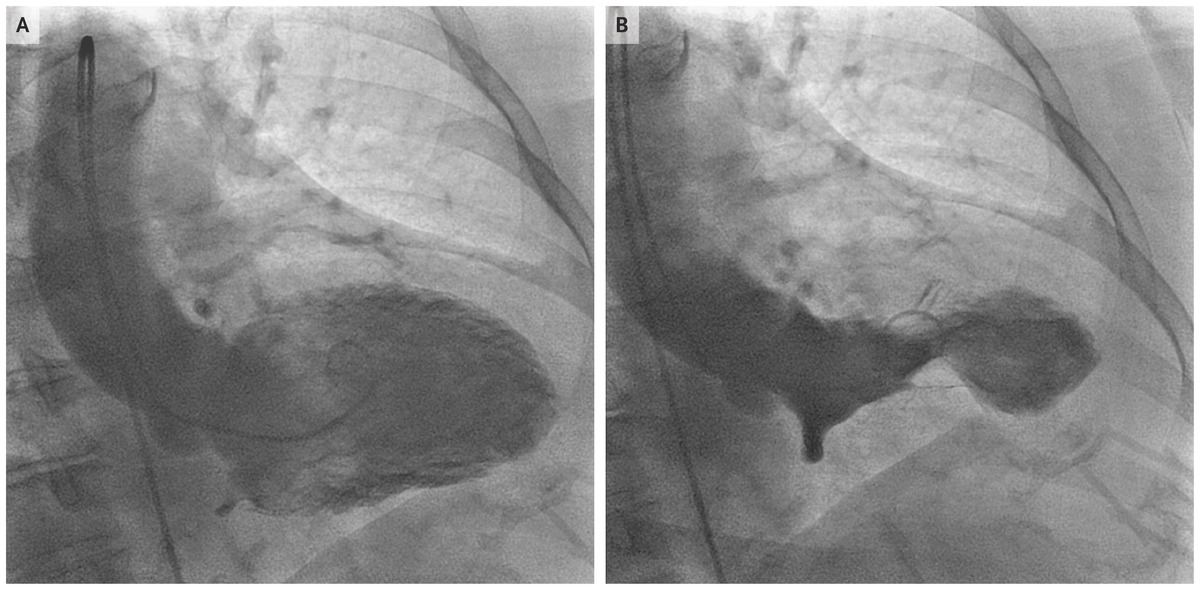

5. Huyết khối tĩnh mạch sâu và huyết khối tắc mạch phổi

Mặc dù những sự kiện này không liên quan trực tiếp đến kỹ thuật gây mê, nhưng đây là một trong những yếu tố có thể liên quan. Đây là những biến chứng đáng sợ nhất trong phẫu thuật và thường xảy ra hơn trong hút mỡ và phẫu thuật tạo hình bụng.

Tắc mạch có thể là huyết khối hoặc mỡ. Các yếu tố nguy cơ là phụ nữ trẻ, sử dụng thuốc tránh thai, đi máy bay hơn 6-8 giờ, phẫu thuật kéo dài và bệnh lý huyết khối như yếu tố V Leiden.

Các biện pháp phòng ngừa bằng vớ đàn hồi và nén khí, vận động sớm, thuốc chống kết tập tiểu cầu, heparin và / hoặc thuốc chống đông đường uống là bắt buộc ở những bệnh nhân có nguy cơ cao vì biến chứng này là nguyên nhân tử vong hàng đầu trong phẫu thuật thẩm mỹ.

Trong 1.141.418 ca phẫu thuật ngoại trú, có 23 ca tử vong, nguyên nhân là thuyên tắc phổi ở 13 bệnh nhân. Phẫu thuật cắt bỏ não là phẫu thuật thường gặp nhất dẫn đến tử vong do thuyên tắc phổi tại một cơ sở phẫu thuật có trụ sở tại văn phòng.